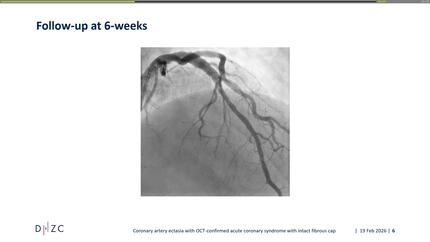

Unexpected findings in a case of Acute myocardial infarction: the angiogram that changed the plan